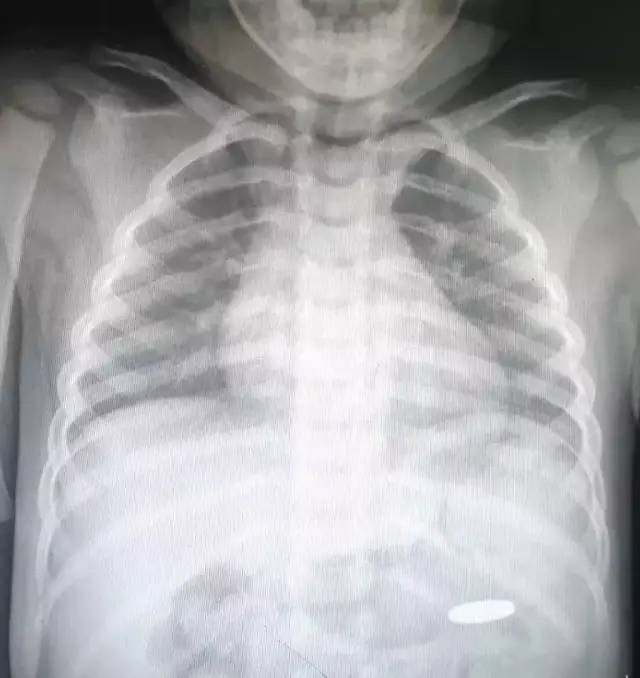

孩子吃了坚果,如花生、瓜子等小而硬的食物,或者玩小件玩具、物品后出现呛咳、憋气、面部青紫时,我们就要高度警惕了,要仔细听孩子呼吸音是否变粗,有没有喘鸣。

有的孩子误吞异物时我们不在身边未能及时发现,或者异物较小,呛入时可能没有明显的症状,这种情况虽然当时没有明显的表现,但是孩子不久就可能出现顽固性咳嗽、发热、黏痰等症状,经过药物治疗反复不见好转的,就要怀疑气道异物的可能!

异物卡喉指的是异物卡到了气管,气管是我们用来呼吸的通道,如果气管被完全卡死了,我们便无法呼吸,窒息会导致死亡。